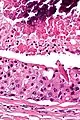

Intermed. mag.

Their histologic appearance is similar to ductal breast carcinoma.